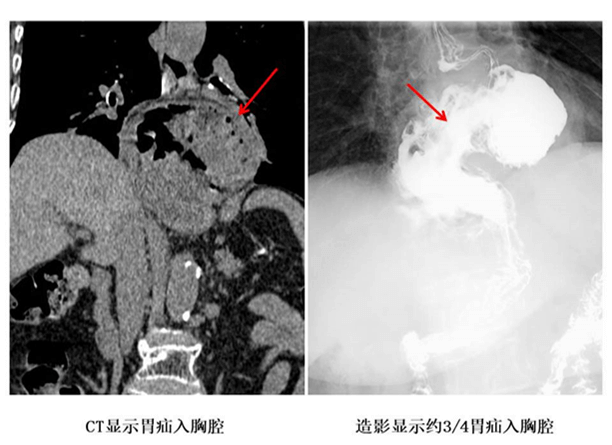

患者为老年女性,二十多年来饱受反酸、烧心等症状困扰,近期因病情加重,出现进食困难。经检查,其胃疝入胸腔,诊断为“食管裂孔疝”。若得不到及时有效治疗,将严重影响其营养状况与生活质量。

依托我院与安医大一附院建立的医联体协作平台,省级优质医疗资源得以直接下沉。喻鑫教授与我院外一科团队共同为患者制定了周密的手术方案,并成功实施了“腹腔镜下食管裂孔疝修补术+胃底折叠术”。手术仅通过腹部数个微小切口完成,在腹腔镜精准操作下,将疝入胸腔的胃体还纳至腹腔,修补扩大的食管裂孔,并进行了抗反流处理。手术过程顺利,出血极少,实现了微创与疗效的最佳结合。